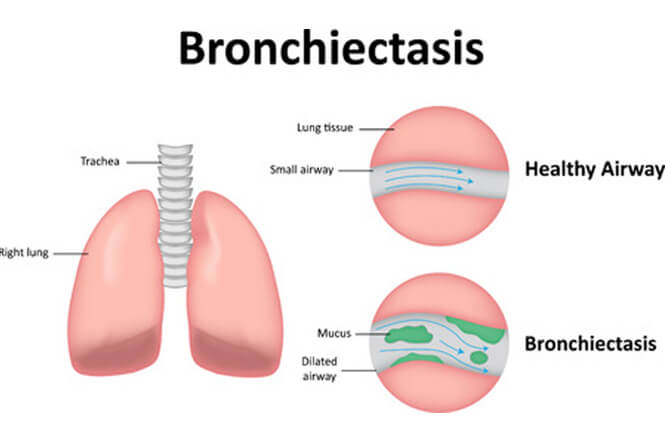

Respiratory diseases

Respiratory diseases are conditions that affect any of the processes involved with breathing. If you or someone you know are one of the 1 in 6 New Zealanders that lives with a respiratory condition, here you can find some useful information on how to manage the condition well.